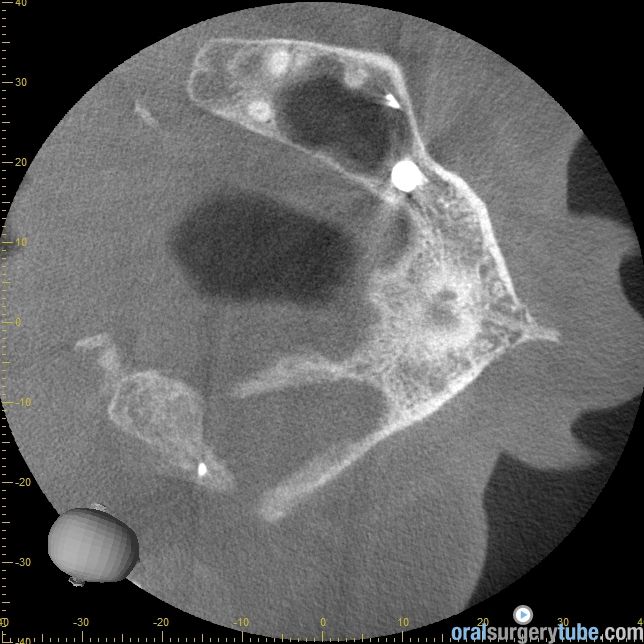

Cierre de comunicación orosinusal con tejido duro y blando